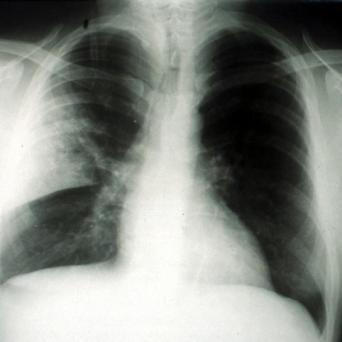

L’image

du jour

Illustration.